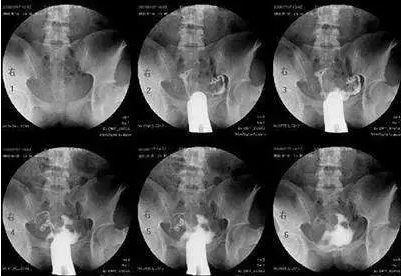

當(dāng)然,以上說的都是可能性的癥狀,并不代表有這些癥狀就一定是輸卵管有問題的。如果有這些癥狀,要適度警惕一下。當(dāng)然,您也不需要太擔(dān)憂,最好還要結(jié)合多種情況綜合考慮,如果實在不放心,可以去醫(yī)院做做輸卵管造影術(shù),或者做輸卵管通水、腹腔鏡檢查、輸卵管鏡檢查等。

最常用的是輸卵管碘油造影(HSG)

醫(yī)生會根據(jù)不孕的時間、可能的原因,來選擇是否需要做造影。

造影的時間一般在月經(jīng)干凈后3天到排卵之前,造影前不要有性生活,白帶檢查正常等等。造影后1周禁性生活,當(dāng)月最好不要嘗試懷孕。

不過現(xiàn)在的造影劑比較先進(jìn),一般代謝很快,假如不小心當(dāng)月懷上,多數(shù)也沒有問題。保險一點(diǎn),等下次月經(jīng)來過再試孕。